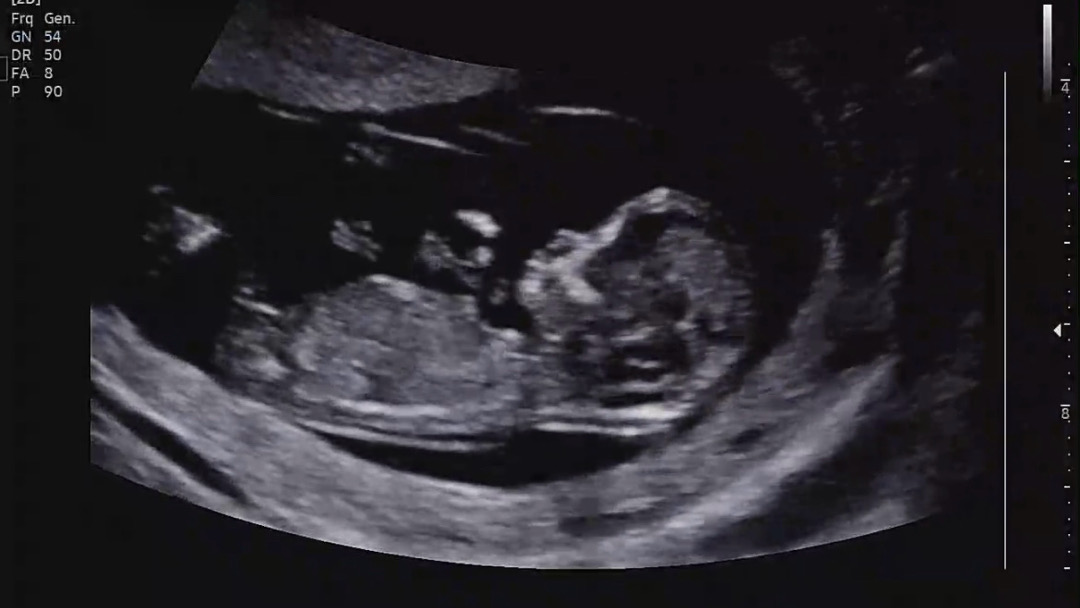

각도법 봐주세요!!🙏🏻🙏🏻

아들일까요 딸일까요🥹

끝부분이 갈라져있는걸로 보이는데 그럼 딸이라 하네요 : )